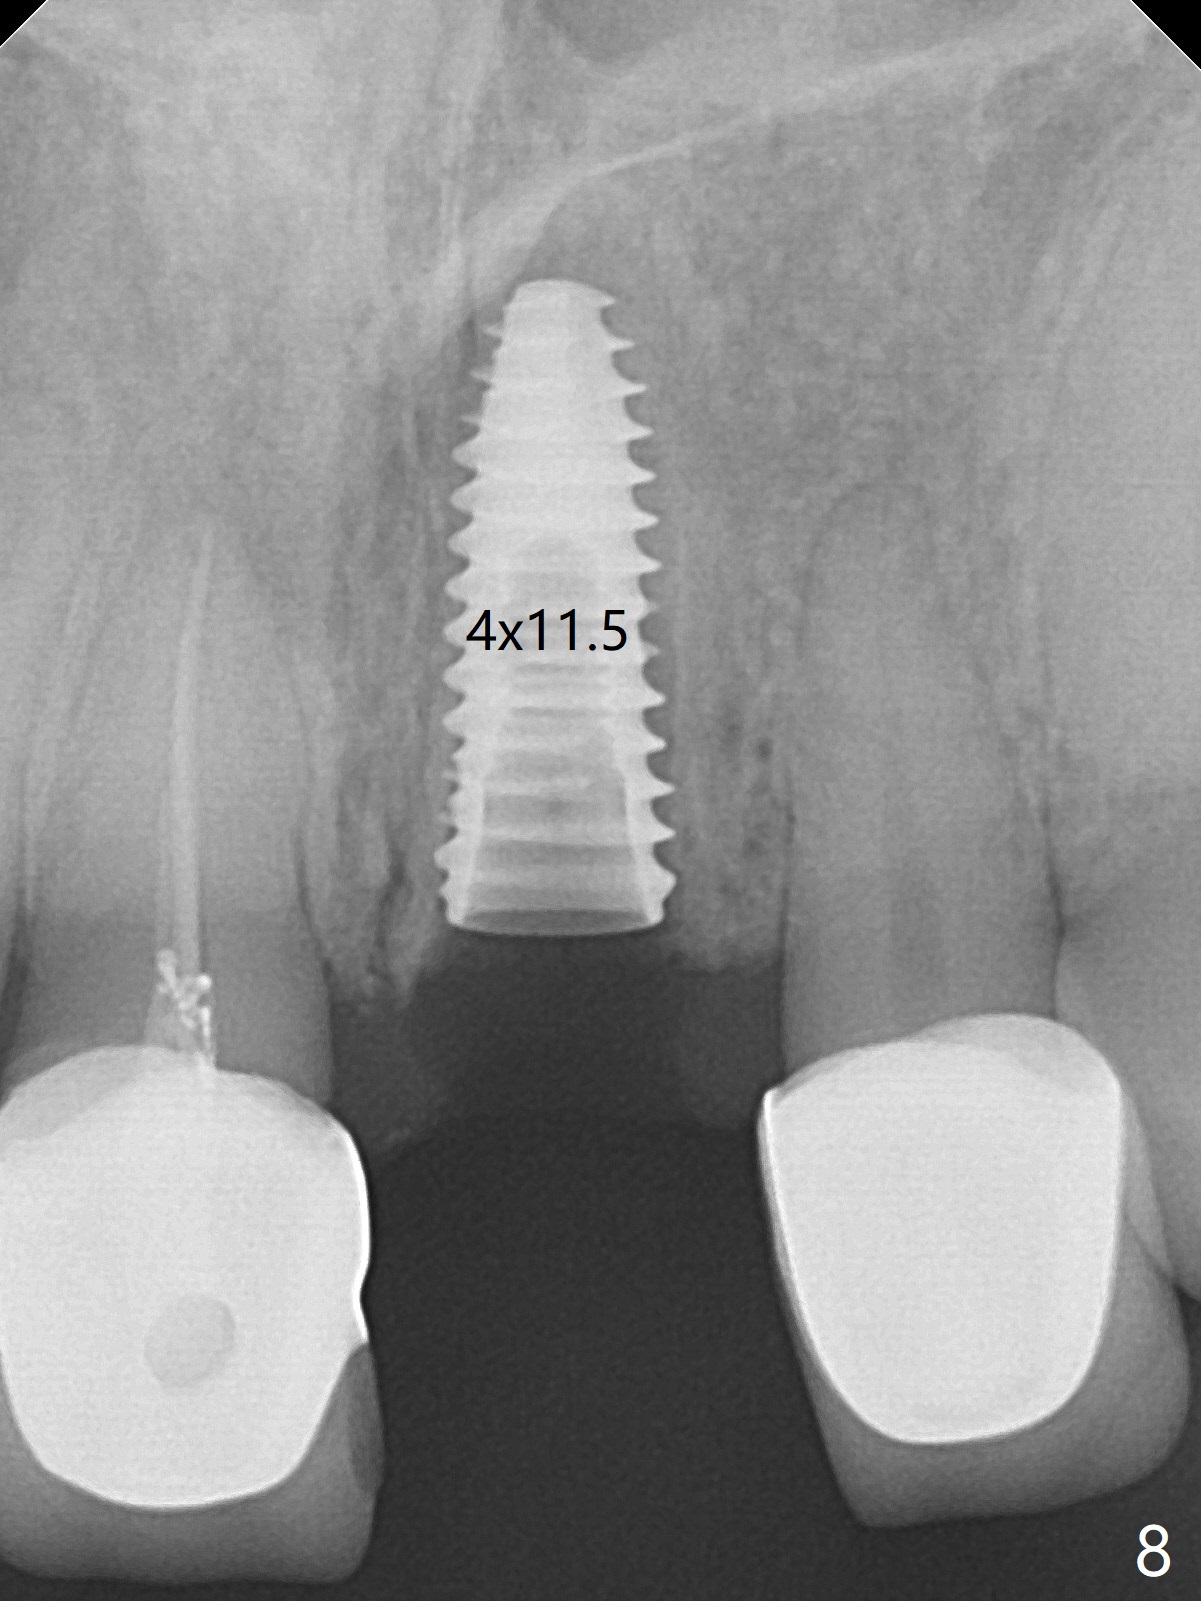

After sectioning the splinted crowns at #8 and 9 (Fig.1,2 (*: open bite)), the tooth #9 is deemed nonsalvageable because of caries and the crown/retainer of #8 is recemented. The trajectory of initial osteotomy is off (Fig.3 (red line: ideal trajectory)). Using Lindamann bur twice does not improve the trajectory (Fig.4,5). It appears that a new osteotomy should be established in the distal wall of the socket (Fig.5 red line (initial entry point and angle), Fig.6). Following sequential osteotomy, a 4x10 mm dummy implant is placed with stability and ~ 3.5 mm apical space (Fig.7 red line). A final implant (4x11.5 mm) is placed subcrestal (except buccal, Fig.8). With further placement of the implant, a 4.5x5.5(3) mm abutment and Vera graft are placed (Fig.9) prior to fabrication of an immediate provisional. In all, a new osteotomy site should be set up when the trajectory is to be changed substantially. There is no gross bone loss 4.5 months postop (Fig.10). There is shade mismatch when a porcelain-fused-Zirconia crown is tried in (Fig.11, as compared to Fig.1). The latter is corrected when a PFM crown is cemented (Fig.12).